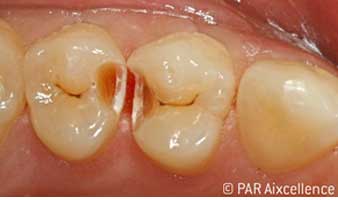

Рис. 1. Начальный вид зубов без клинических признаков кариеса